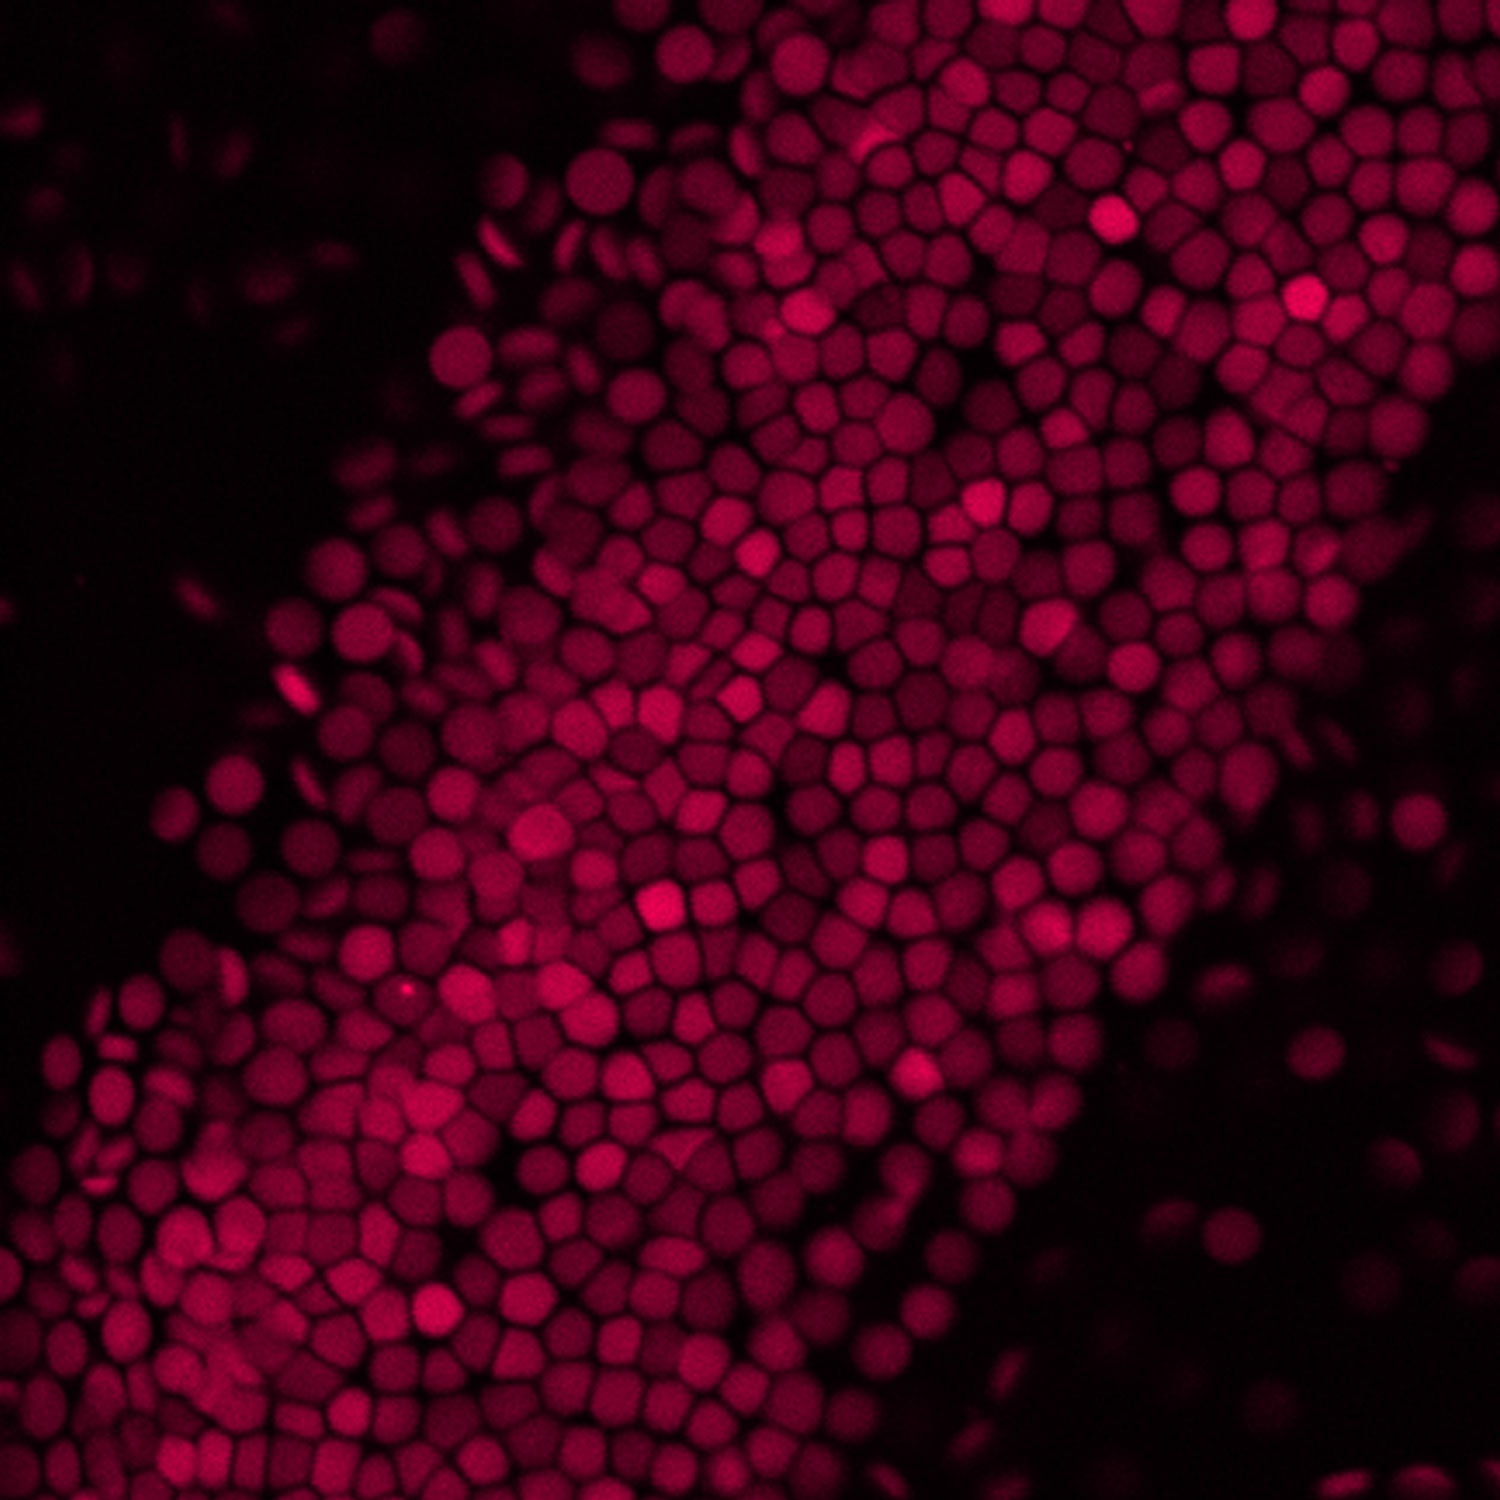

Structural Surfaceomics Reveals an AML Specific Conformation of Integrin-β2 as an Immunotherapeutic Target

First author Kamal Mandal, PhD, discusses how the research team explored the hypothesis that tumor surface antigens may harbor cancer-specific protein conformations, invisible to standard target discovery strategies focusing on gene or protein expression alone, that may create selective immunotherapy targets. Their results underscore the potential of “structural surfaceomics” to expand the toolkit of target discovery in cancer, with possible applications in other diseases, while motivating further preclinical evaluation of aITGB2 CAR-Ts in acute myeloid leukemia (AML). Mandal is a UCSF postdoctoral scholar working in the Arun Wiita Lab. Arun Wiita, MD, PhD, is senior author of the study and an associate professor of laboratory medicine at UCSF.

Abstract 357